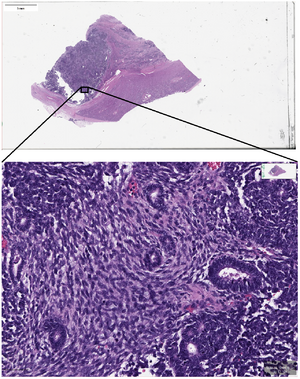

Digital pathology is a sub-field of pathology that focuses on data management based on information generated from digitized specimen slides. Through the use of computer-based technology, digital pathology utilizes virtual microscopy.[1] Glass slides are converted into digital slides that can be viewed, managed, shared and analyzed on a computer monitor. With the practice of Whole-Slide Imaging (WSI), which is another name for virtual microscopy,[2] the field of digital pathology is growing and has applications in diagnostic medicine, with the goal of achieving efficient and cheaper diagnoses, prognosis, and prediction of diseases due to the success in machine learning and artificial intelligence in healthcare.

Trained pathologists traditionally view tissue slides under a microscope. These tissue slides may be stained to highlight cellular structures. When slides are digitized, they are able to be shared through tele-pathology and are numerically analyzed using computer algorithms. Algorithms can be used to automate the manual counting of structures, or for classifying the condition of tissue such as is used in grading tumors. They can additionally be used for feature detection of mitotic figures, epithelial cells, or tissue specific structures such as lung cancer nodules, glomeruli, or vessels, or estimation of molecular biomarkers such as mutated genes, tumor mutational burden, or transcriptional changes.[15][16][17] This has the potential to reduce human error and improve accuracy of diagnoses. Digital slides can be easily shared, increasing the potential for data usage in education as well as in consultations between expert pathologists. Multiplexed imaging (staining multiple markers on the same slide) allows pathologists to understand finer distribution of cell-types and their relative locations.[18] An understanding of the spatial distribution of cell-types or markers and pathways they express, can allow for prescription of targeted drugs or build combinational therapies in a personalized manner.